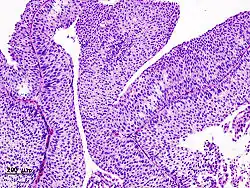

![]() | Dysgerminoma | Dysgerminoma characterized by uniform cells resembling primordial germ cells separated by fibrous septa with lymphocytes. | Category: Histopathology of ovarian dysgerminoma | Ovarian dysgerminoma |